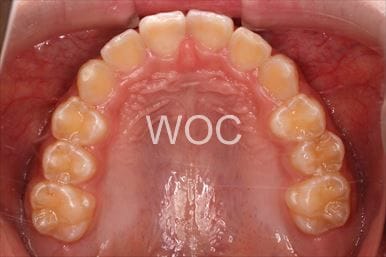

治療後1

-

治療後2

-

治療後3

-

治療後4

-

治療後5

- 年齢:22歳女性

- 主訴:出っ歯、前歯で噛み切れない

- 基本矯正料金:85万円

- 治療期間:1年4ヶ月

- 非抜歯